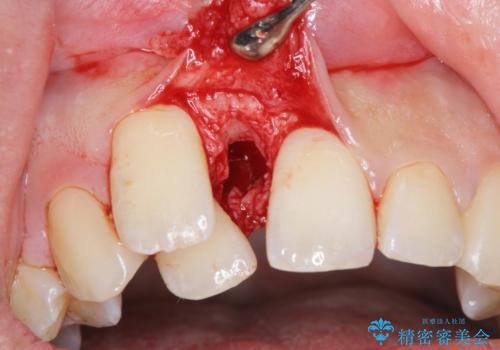

正中過剰埋伏歯で生じた前歯の審美障害 矯正治療での改善

- 前歯の見た目に悩まれて来院されました。

当初他院では、抜歯を行いセラミックブリッジを提案されていましたが、他の方法はないかと総合歯科治療を行う当院へと相談来院されました。

「時間がかかっても良いので、できれば歯を抜かずに矯正治療で治したい。」という強い希望があったので、矯正治療で歯並び・審美性の改善を計画します。